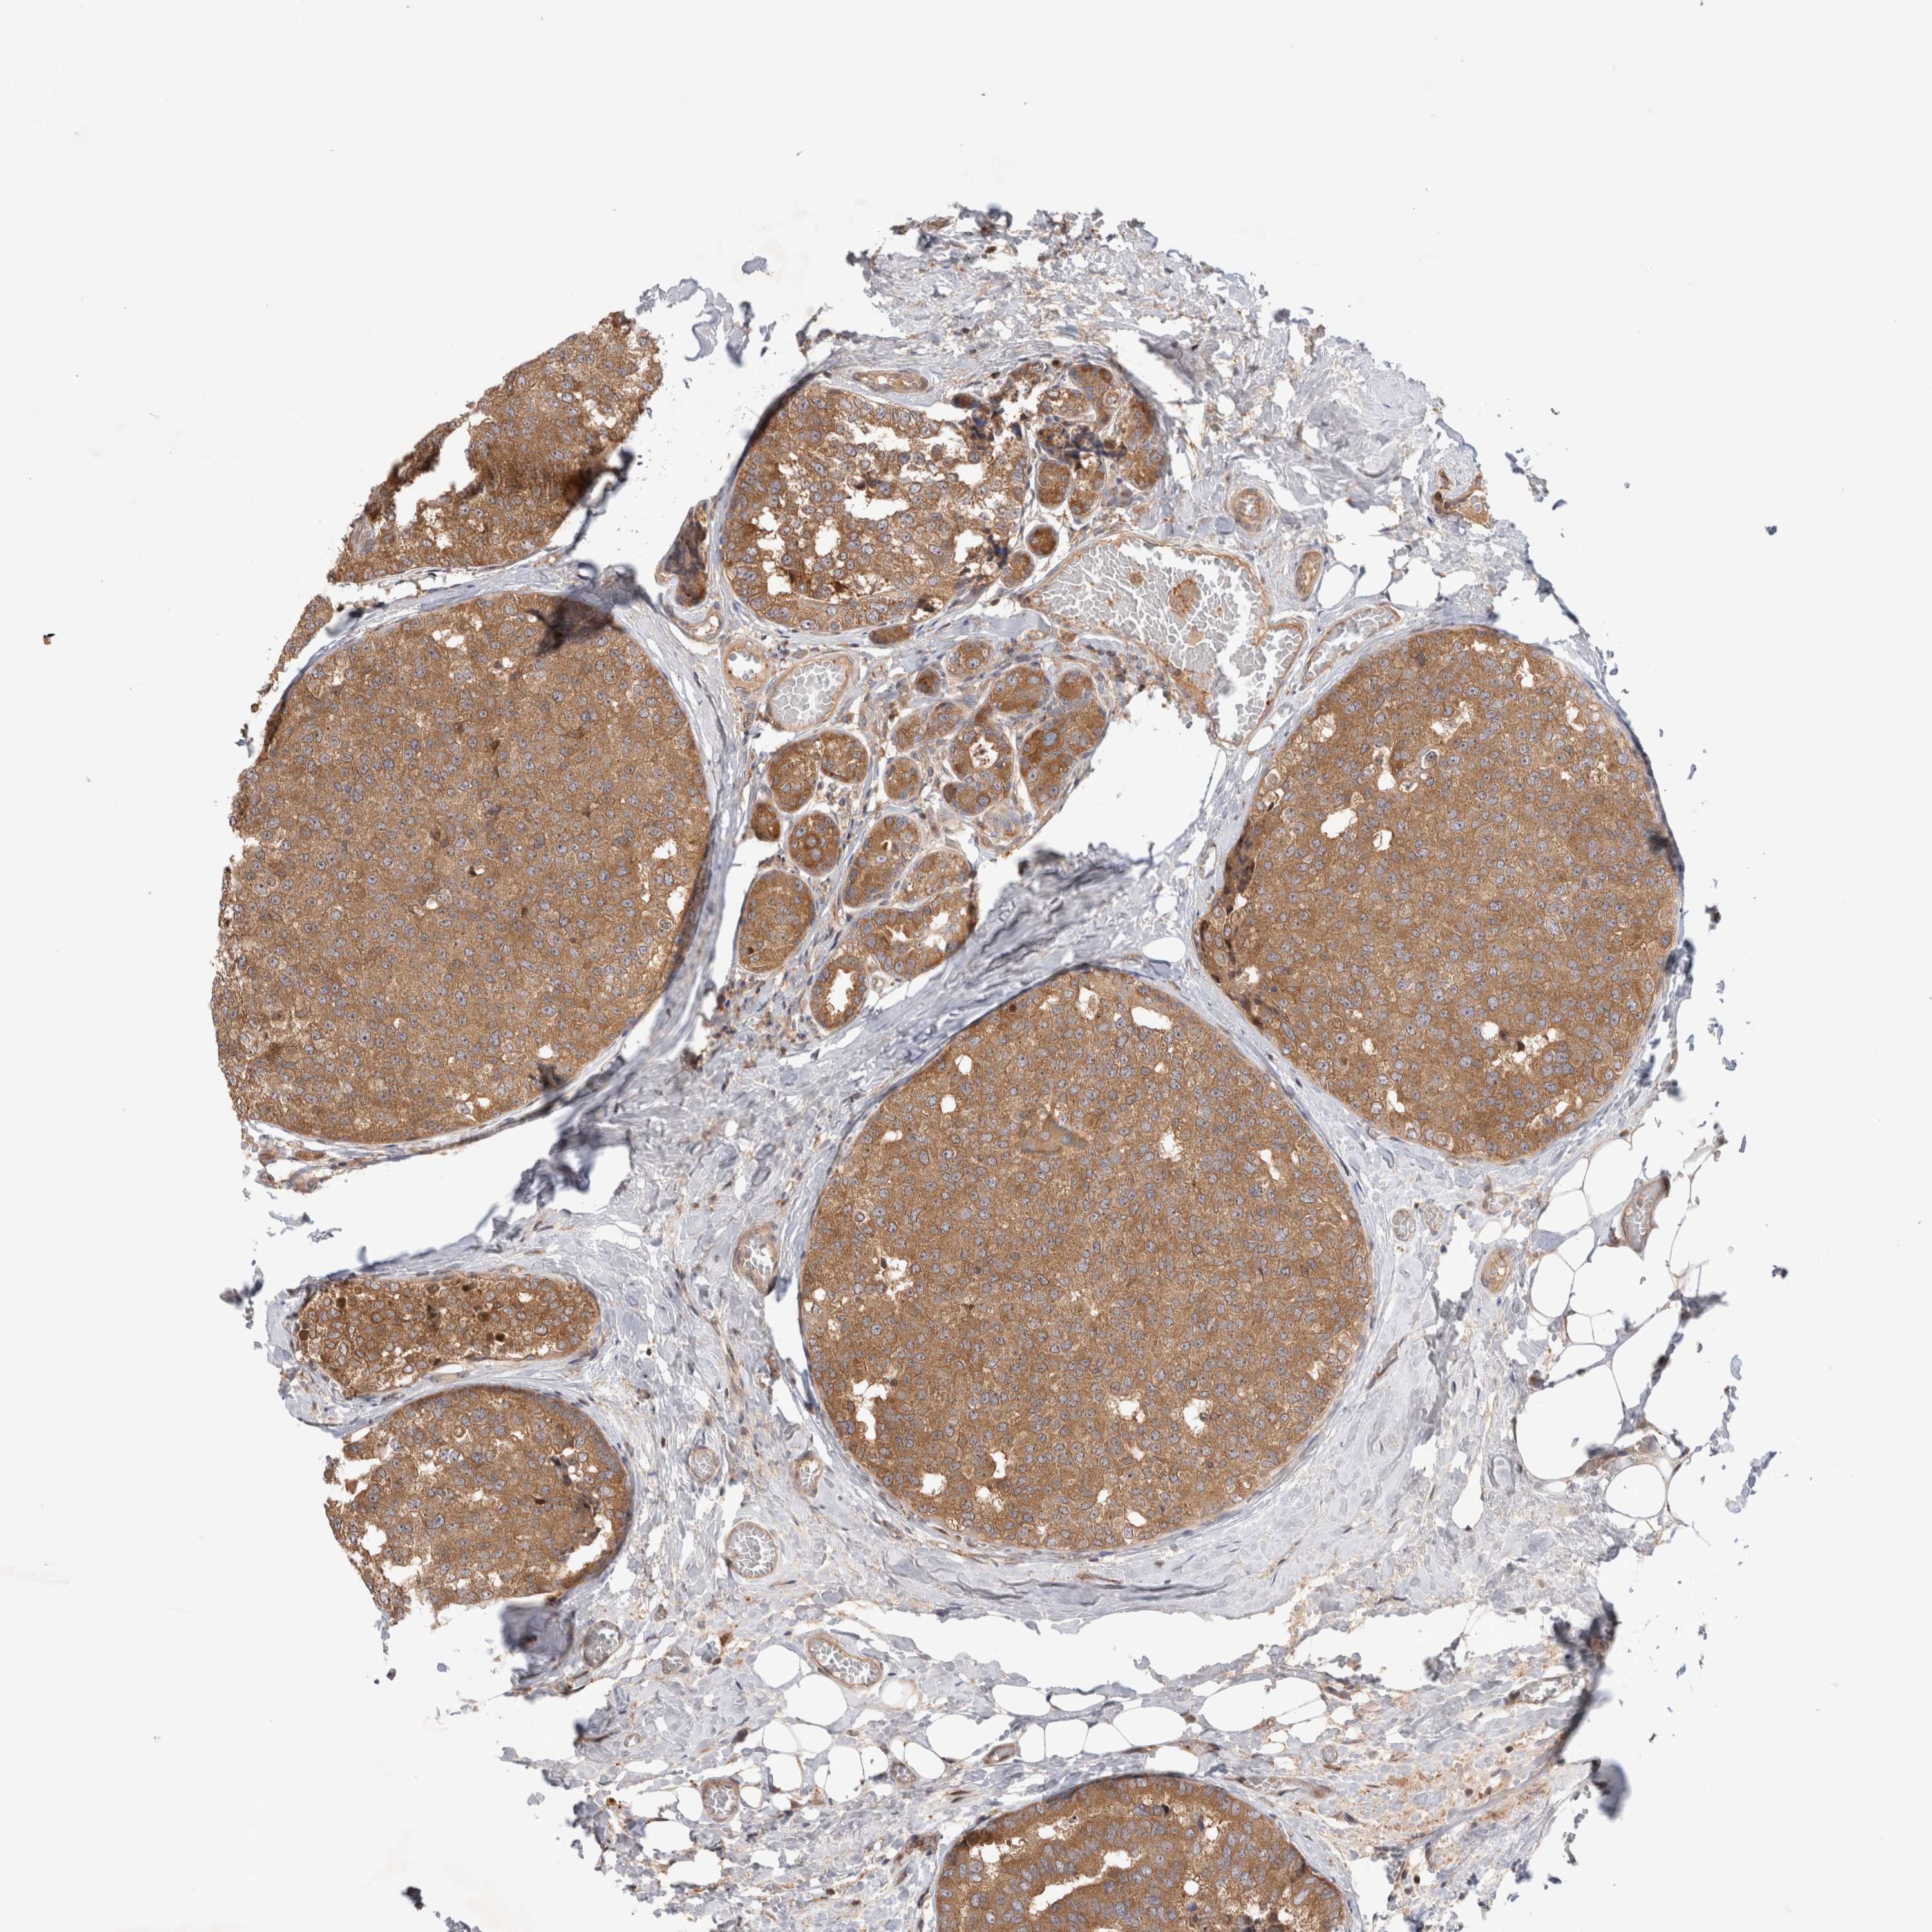

CANCER BREAST CANCER Show tissue menu

BRCA TCGA BRCA VALIDATION PROTEIN EXPRESSION